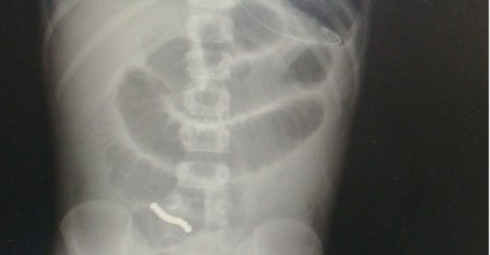

Ребенку сделали рентген брюшной полости и поняли всю тяжесть состояния. "На снимке была выявлена закупорка кишечника множественными инородными телами, соединившимися в цепочку, - говорит д-р Кейдар. - Магниты сцепились друг с другом в толстом и тонком кишечнике, и в течение 3 дней развились гангрена и перфорация стенок кишечника. В кишечных петлях мы нашли 5 отверстий. Такое крайне опасное состояние было вызвано тем, что мальчик проглотил магниты".